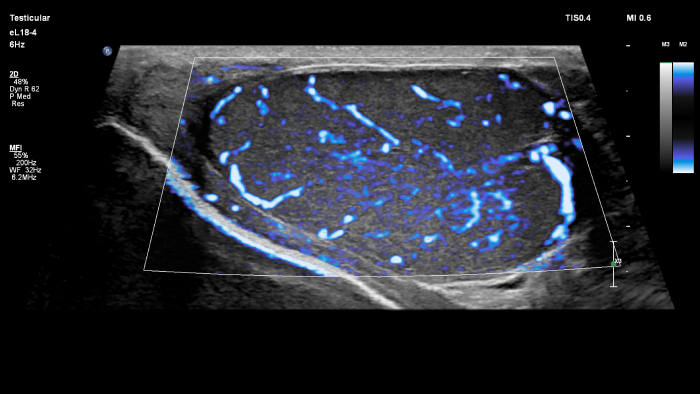

O MicroFlow Imaging ultrapassa muitas das barreiras associadas aos métodos convencionais para a deteção do fluxo sanguíneo de vasos pequenos com alta resolução e artefactos mínimos.